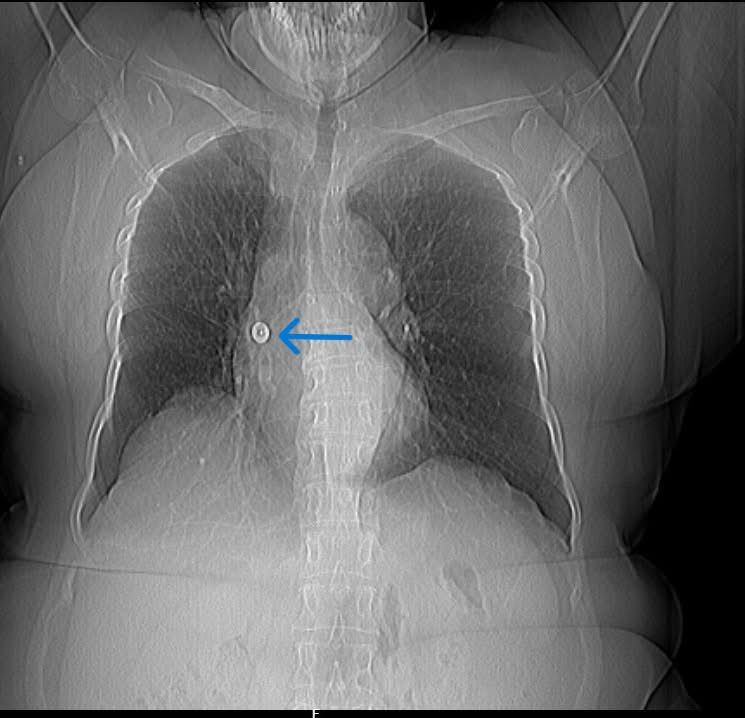

Upon her visit to Aster CMI Hospital, detailed imaging through CT scan and chest X-ray revealed the presence of a foreign object firmly attached to the bronchial wall. The complexity of the case required a highly precise and cautious approach.

Dr. Sunil Kumar K, Lead Consultant – Interventional Pulmonology at Aster CMI Hospital: saidthe pin’s sharp end had punctured into the airway wall. Standard retrieval methods failed due to the risk of further injury. Using a Fogarty balloon, we were able to gently dislodge the object and subsequently retrieve it using rat tooth forceps during bronchoscopy under sedation.